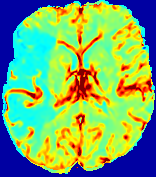

4.3.1 Advection Imaging via Advection-Diffusion

Slice #1Slice #2Slice #3Slice #4Slice #5Slice #6𝐕gt𝟐subscriptnormsuperscript𝐕gt2\|\bf{V}^{\text{gt}}\|_{2}Refer to captionRefer to captionRefer to captionRefer to captionRefer to captionRefer to caption𝐕est𝟐subscriptnormsuperscript𝐕est2\|\bf{V}^{\text{est}}\|_{2}Refer to captionRefer to captionRefer to captionRefer to captionRefer to captionRefer to captionRefer to caption1.51.51.51.21.21.20.90.90.90.60.60.60.30.30.30.00.00.0(mm/s)𝑚𝑚𝑠(mm/s)Destsuperscript𝐷estD^{\text{est}}Refer to captionRefer to captionRefer to captionRefer to captionRefer to captionRefer to captionRefer to caption0.0150.0150.0150.0120.0120.0120.0090.0090.0090.0060.0060.0060.0030.0030.0030.0000.0000.000(mm2/s)𝑚superscript𝑚2𝑠(mm^{2}/s)

Figure 14: PIANO identifiability testing: advection imaging via advection-diffusion. Top row shows 𝐕gt2subscriptnormsuperscript𝐕gt2\|{\bf{V}}^{\text{gt}}\|_{2} used for simulating ground truth pure advection. Rows below show the estimated 𝐕est2subscriptnormsuperscript𝐕est2\|{\bf{V}}^{\text{est}}\|_{2} and Destsuperscript𝐷estD^{\text{est}} on corresponding slices. Note that the plotted value scale for Destsuperscript𝐷estD^{\text{est}} is 0.01 of that for 𝐕gt2subscriptnormsuperscript𝐕gt2\|{\bf{V}}^{\text{gt}}\|_{2} and 𝐕est2subscriptnormsuperscript𝐕est2\|{\bf{V}}^{\text{est}}\|_{2}.

We use the same ‘Advection Imaging’ simulation of Sec. 4.2.1 as the concentration dataset for PIANO. However, instead of modeling pure advection (Eq. 15), we let PIANO estimate both velocity 𝐕estsuperscript𝐕est{\bf{V}}^{\text{est}} and diffusivity Destsuperscript𝐷estD^{\text{est}} via the advection-diffusion PDE (Eq. 2) underlying the proposed PIANO model. Fig. 14 shows the estimated 𝐕est2,subscriptnormsuperscript𝐕est2\|{\bf{V}}^{\text{est}}\|_{2}, and Destsuperscript𝐷estD^{\text{est}} fields for one patient. Although PIANO has the freedom to estimate both a velocity and a diffusivity field from pure advection, PIANO differentiates well between advection and diffusion: the estimated 𝐕est2subscriptnormsuperscript𝐕est2\|{\bf{V}}^{\text{est}}\|_{2} successfully reproduces the ground truth 𝐕gt2subscriptnormsuperscript𝐕gt2\|{\bf{V}}^{\text{gt}}\|_{2} governing the simulated advection process, just as it already did in the ‘Advection Imaging via Advection’ test (Fig. 12). More importantly, the estimated diffusivity Destsuperscript𝐷estD^{\text{est}} is orders of magnitudes smaller than 𝐕est2subscriptnormsuperscript𝐕est2\|{\bf{V}}^{\text{est}}\|_{2}, indicating the estimated diffusion is negligible compared to the estimated advection, which is highly consistent with the underlying pure advection of the simulated data.